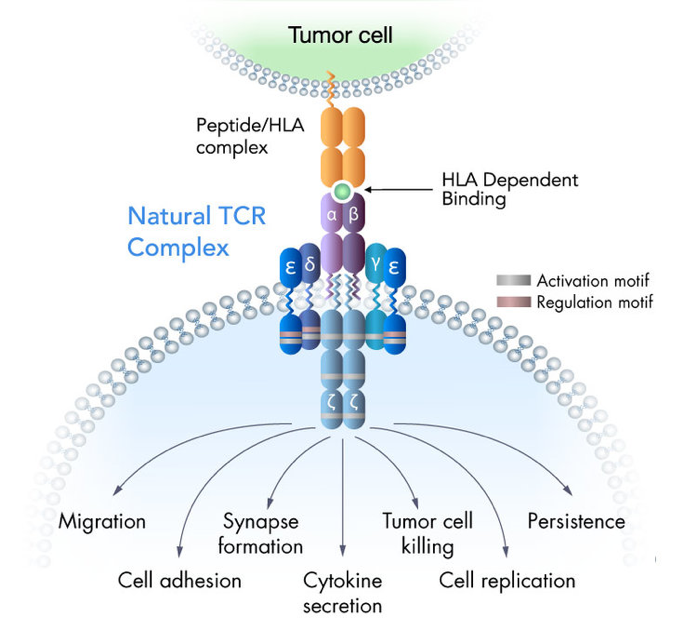

Its proprietary TRuC (TCR Fusion Construct) utilizes the power of T cell signaling pathways and receptors to eliminate cancer cells. This clinical stage immunotherapy company intends to use its T cell therapies to treat hematologic cancers and solid tumors.

Its technology is driven by the TCR complex and phosphorylation motifs (ITAMs) that can bind to tumor antigens and catalyze a complex signaling cascade that can annihilate cancer cells. It’s TRuC™ Platform is an optimal amalgamation of the CAR-T and TCR-T cell therapies minus their shortcomings. It overcomes the limitations of the existing treatment options such as inability to target solid tumors, severe cytokine release syndrome, increased neurotoxicity, HLA down regulation and lack of HLA matching.

The company’s clinical data has shown its superior anti-tumor ability over CAR-T cells with minimal levels of cytokines. It has also demonstrated faster migration to the tumor, improved metabolic fitness and enhanced tumor penetration as compared to CAR – T. Its non-dependence on HLA matching allows it to be used for a larger patient population as well as introduction of improvements to include targeting multiple tumor antigens simultaneously, reduction in treatment expenditure by using off-the-shelf allogenic cells, and accessories to overcome the suppressive effect of the tumor microenvironment.